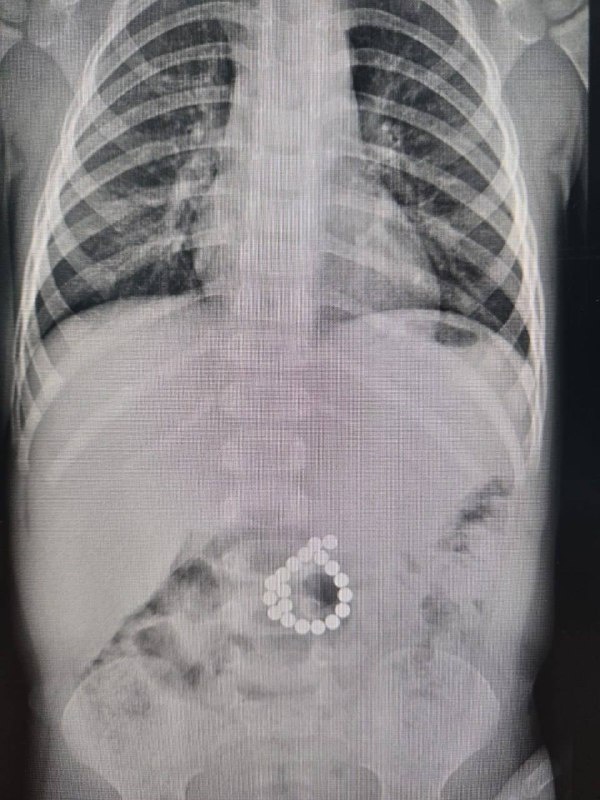

В Сургуте маленький ребенок проглотил 19 магнитов

В Центр охраны материнства и детства поступил двухлетний мальчик с жалобами на сильную боль в животе, высокую температуру. Мама рассказала, что за два дня до появления острых болей в животе сын играл с магнитным конструктором. Операционная бригада под руководством детского хирурга отделением Эльнура Джафарова провела экстренную верхнесрединную лапаротомию. «То, что врачи увидели, подтвердило опасения: 19 магнитов, оказавшихся в толстой кишке, сомкнулись, буквально «прокусив» стенку. В результате возникла двойная перфорация стенки кишки – крайне опасное, жизнеугрожающее состояние, которое привело к развитию инфекции и воспаления брюшной полости», - рассказали в пресс-службе Центра охраны материнства и детства. Врачи удалили инородные тела и ушили дефекты. Малыш идет на поправку.